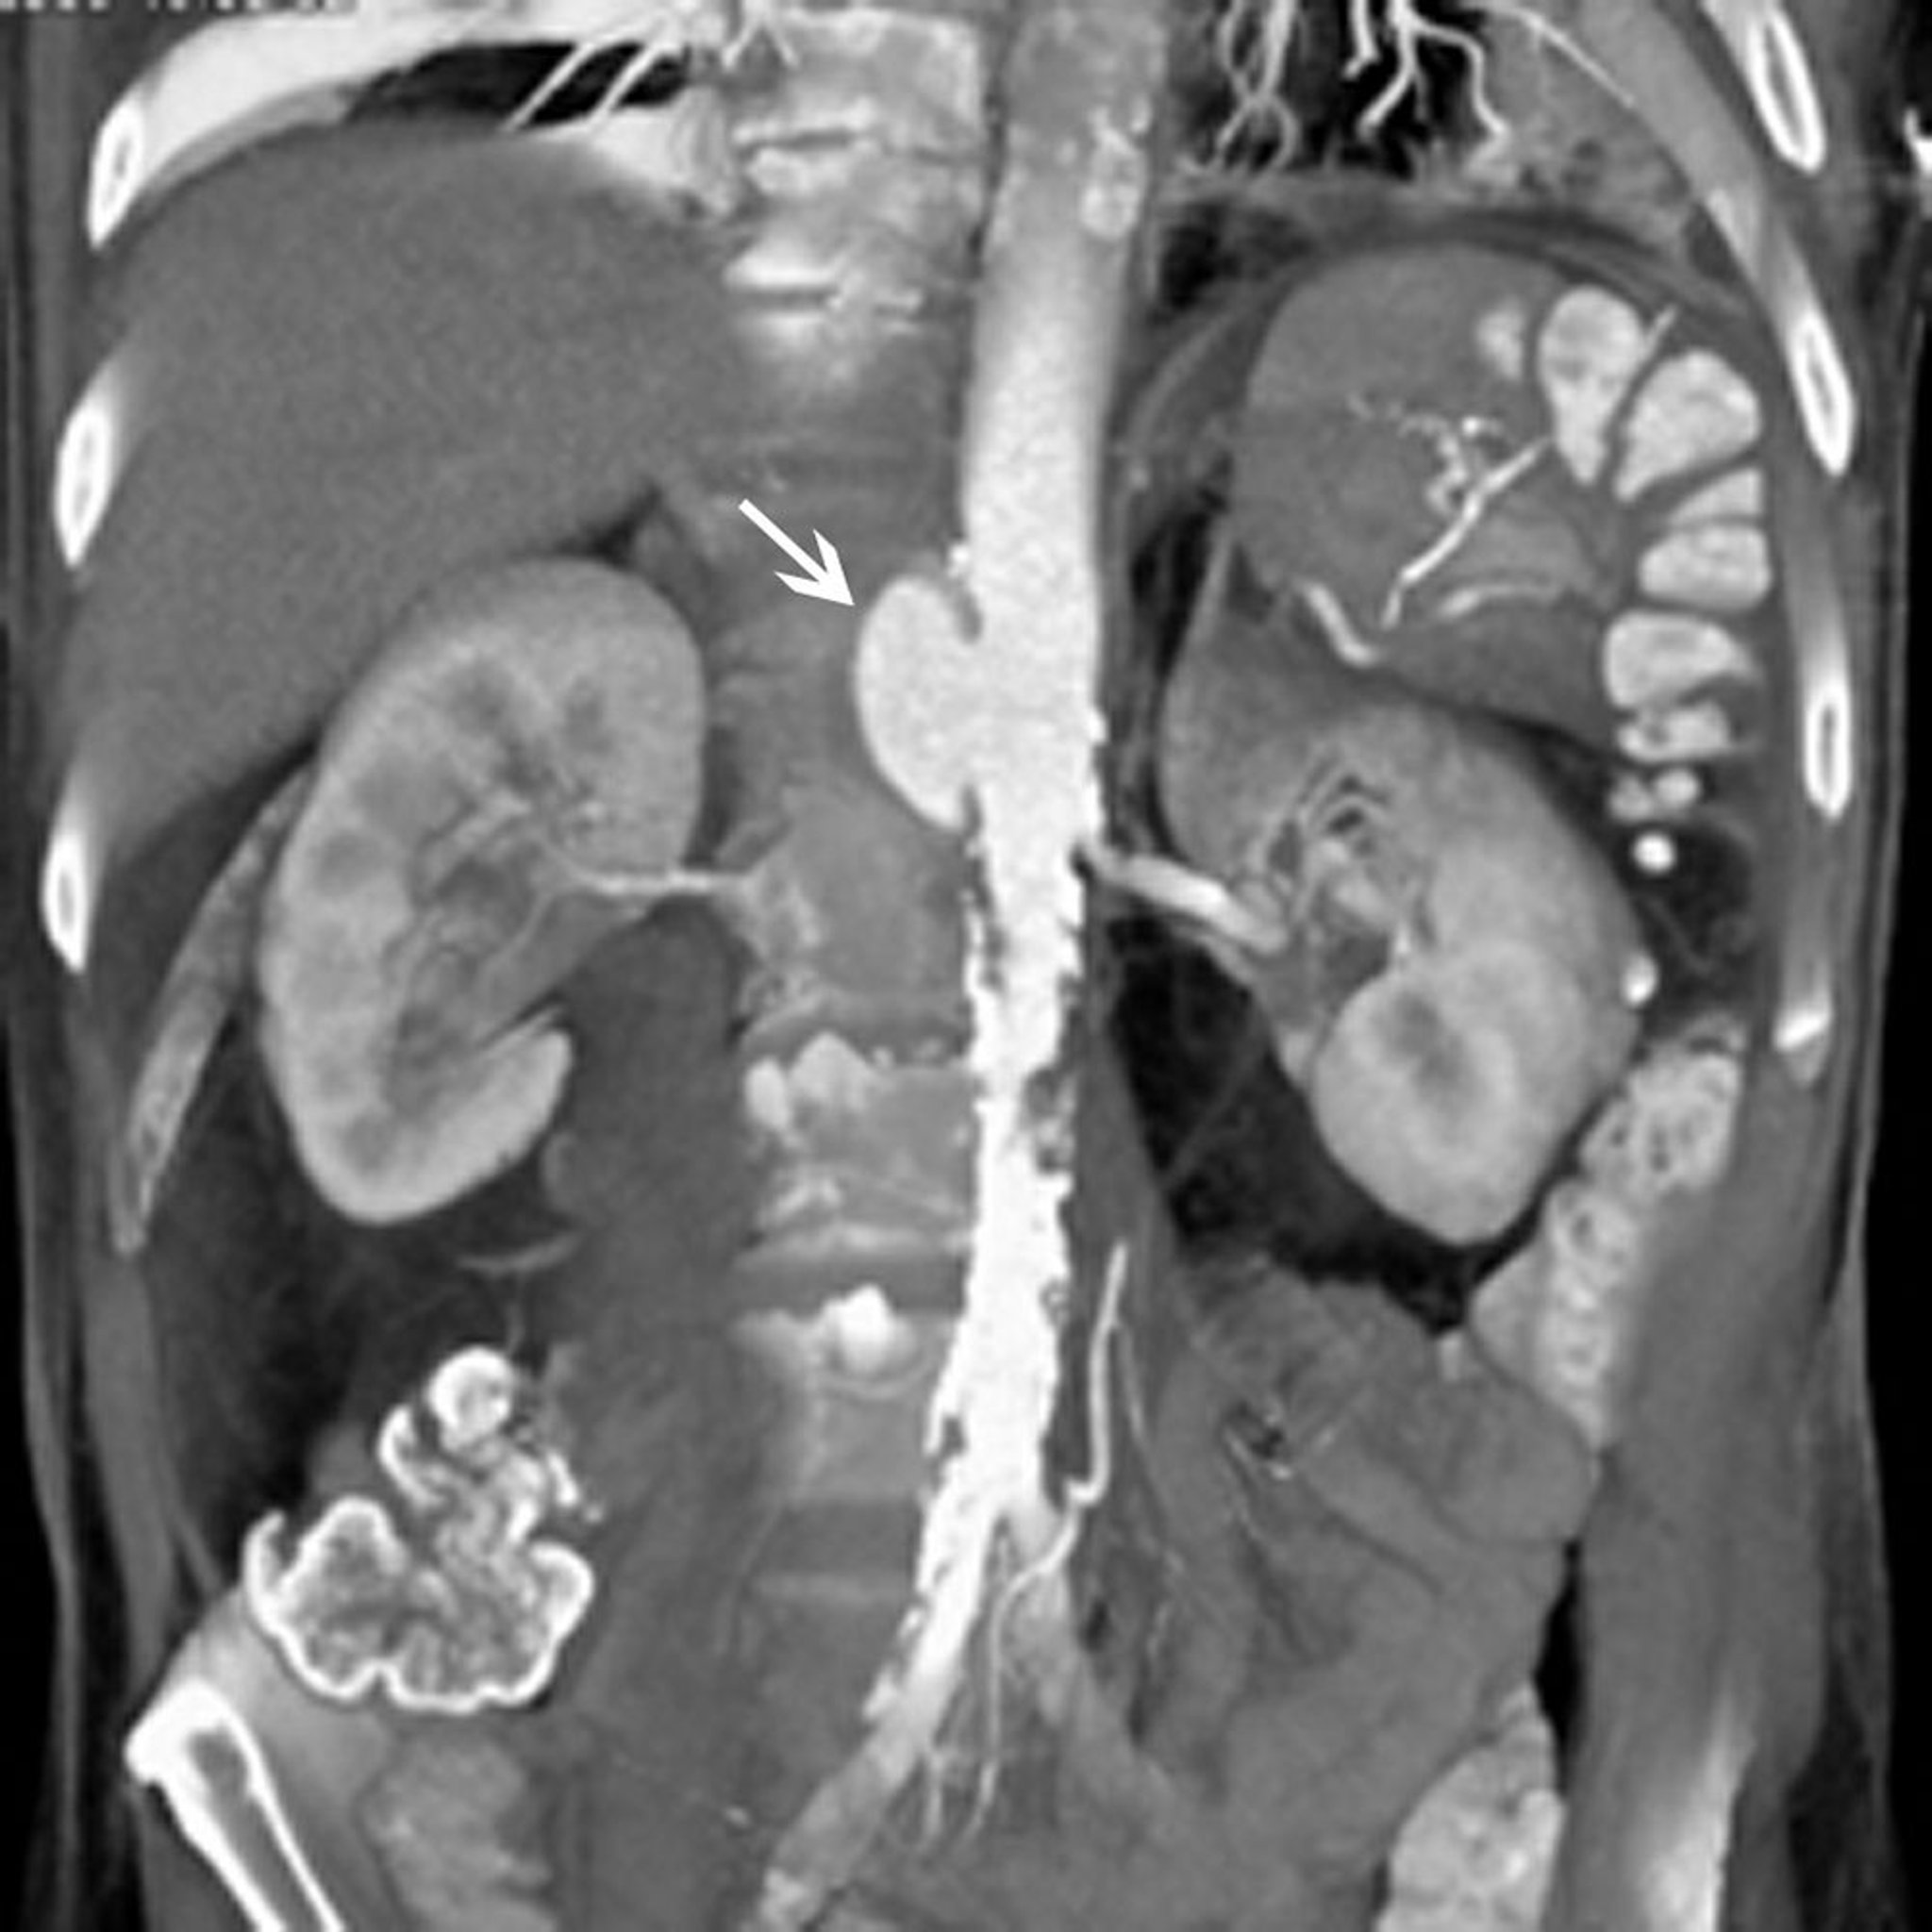

Pseudo-anévrisme de l'aorte abdominale (TDM)

La flèche blanche montre un pseudo-anévrisme de l'aorte abdominale suprarénale. Il existe également une plaque étendue dans l'aorte sous-rénale et les artères iliaques.